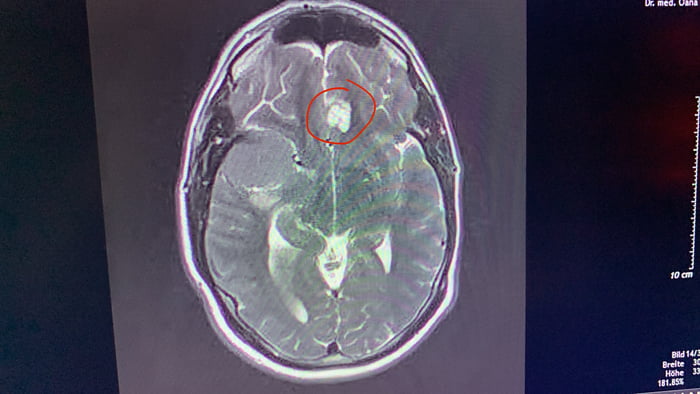

It\u2019s time to win a fight against a brain tumor now - thank u 9gag for how you brighten my days

tumor

cancer